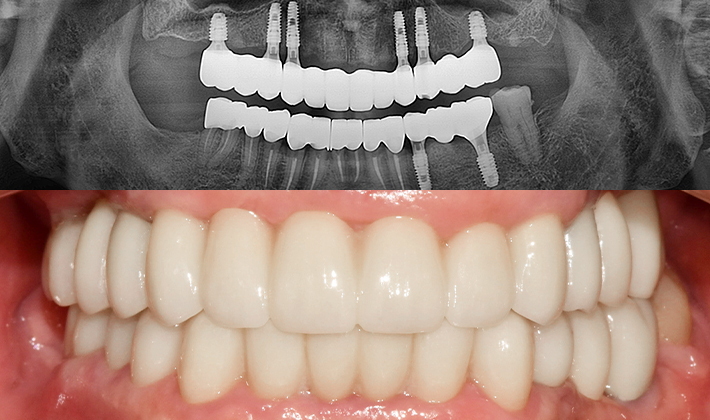

치과가 무서워 10년 동안 미뤄온 임플란트 수술 그 결과는?

2026.01.21